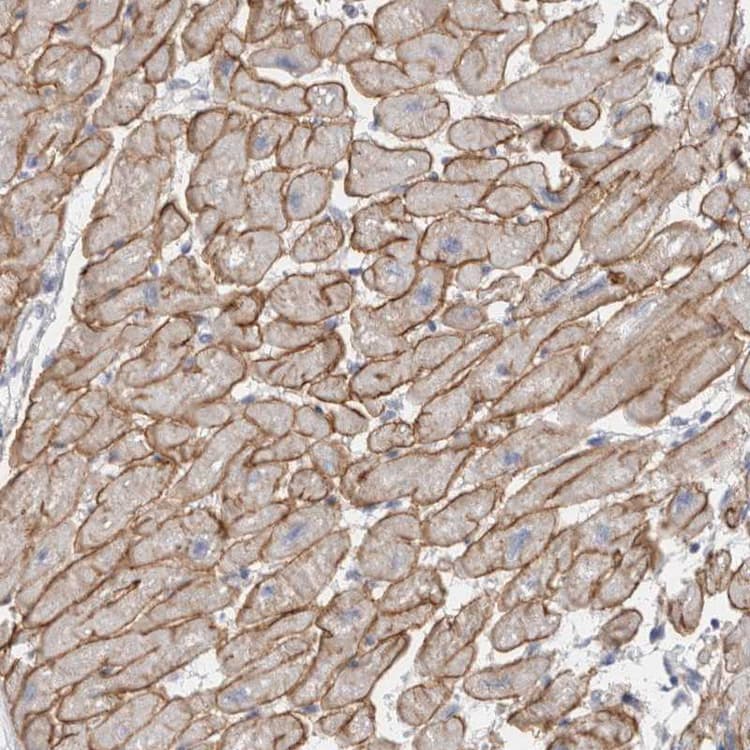

Rabbit Polyclonal Dystrophin antibody. Suitable for IHC-P and reacts with Human samples. Immunogen corresponding to Recombinant Fragment Protein within Human DMD aa 2800-3000.

Applications IHC-P

Species Reactivity Human